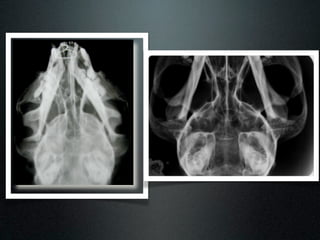

Exame radiográfico

Ventrodorsal

Látero-lateral oblíquo